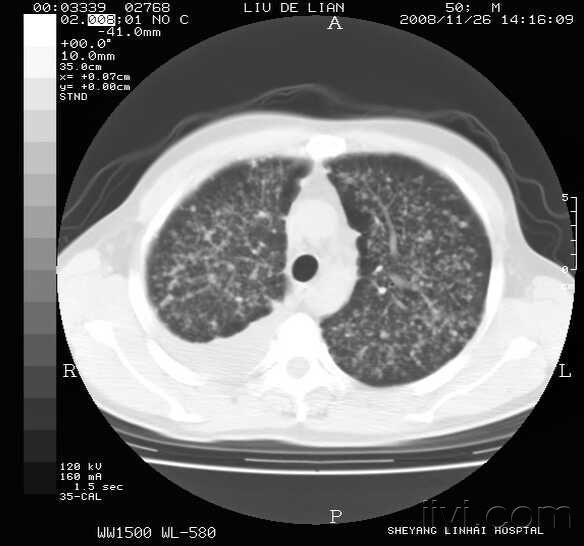

这是弥漫型肺癌的肺窗其中一幅图,请问这个图存在癌性空洞吗?